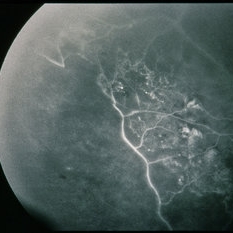

BRVO - Massive Exudate from Collaterals

Feb 24 2014 by David Callanan, MD

66-year-old female with BRVO - massive exudate from collaterals, 20/70 OD; 20/25 OS in 1985; +HTN, glaucoma; 20/200 OD 1987.

Condition/keywords: branch retinal vein occlusion (BRVO), collaterals, exudate